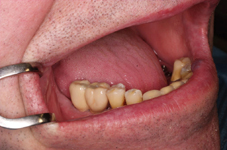

V případě chybění většího počtu zubů v postranních úsecích čelistí je možné ošetření pomocí implantátů, které nahradí ošetření pomocí snímacích náhrad kotvených na zbývajících zubech nebo patře.

Podmínkou je opět dostatečné množství kosti.

Protetické řešení může být pomocí můstku, který je kotvený na implantátech nebo pomocí jednotlivých korunek na implantátech.

V zásadě je možné do těchto můstků zařadit i přirozené zuby, zejména pokud je potřeba tyto zuby ošetřit proteticky

- korunkami. Korunky nebo můstky mohou být na implantáty nacementovány nebo přišroubovány.

Zdravé zuby zůstanou zachovány a přitom náhrady jsou pevné, jako na vlastních zubech